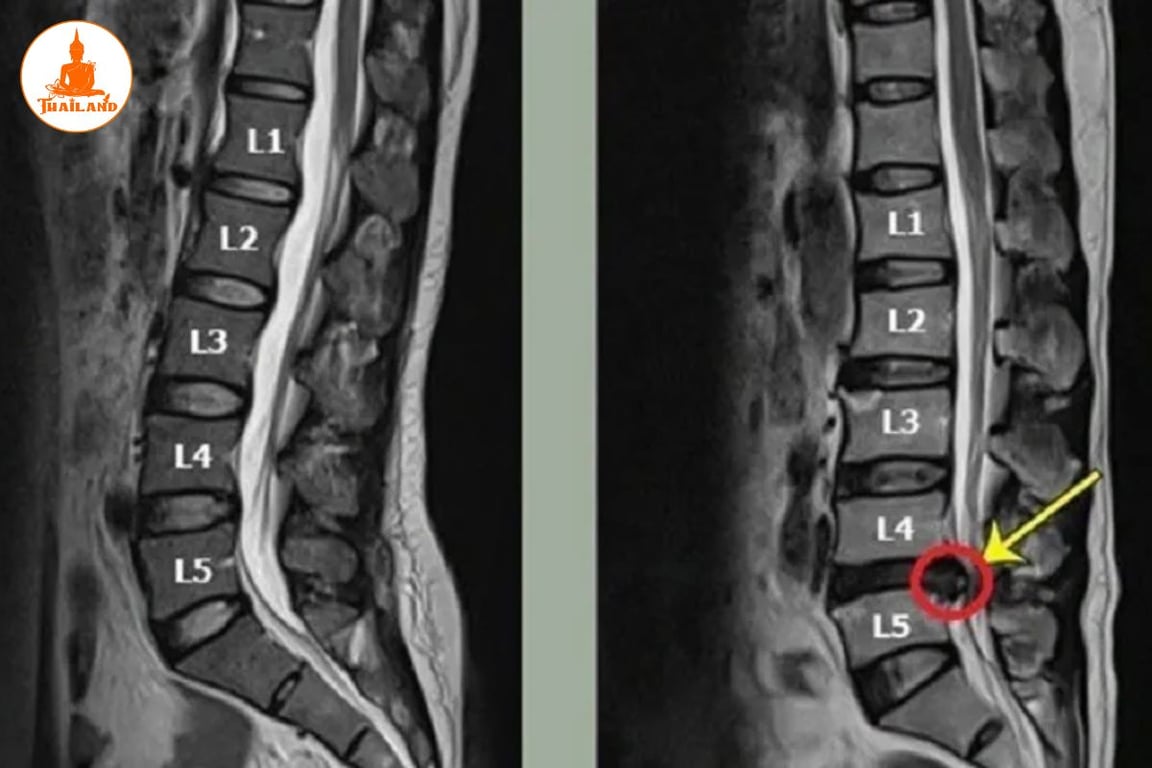

Dựa theo phân loại nêu trên, thoát vị đĩa đệm L4, L5 là tình trạng xảy ra ở hai đốt sống cuối của vùng thắt lưng. Tình trạng này xuất hiện khi nhân nhầy của đĩa đệm nằm giữa hai đốt L4 và L5 bị đẩy ra ngoài, gây chèn ép vào các dây thần kinh, từ đó dẫn đến các cơn đau nhức tại khu vực cột sống.

Chẩn đoán thoát vị đĩa đệm L4, L5

Chụp cộng hưởng từ (MRI): Là phương pháp có độ chính xác cao trong việc phát hiện thoát vị đĩa đệm vì hình ảnh thu được thể hiện rõ các mô mềm như đĩa đệm, dây chằng và rễ thần kinh.

Dựa trên kết quả từ các phương pháp chẩn đoán hình ảnh này, bác sĩ sẽ đưa ra phác đồ điều trị phù hợp với mức độ và tình trạng cụ thể của từng người bệnh.